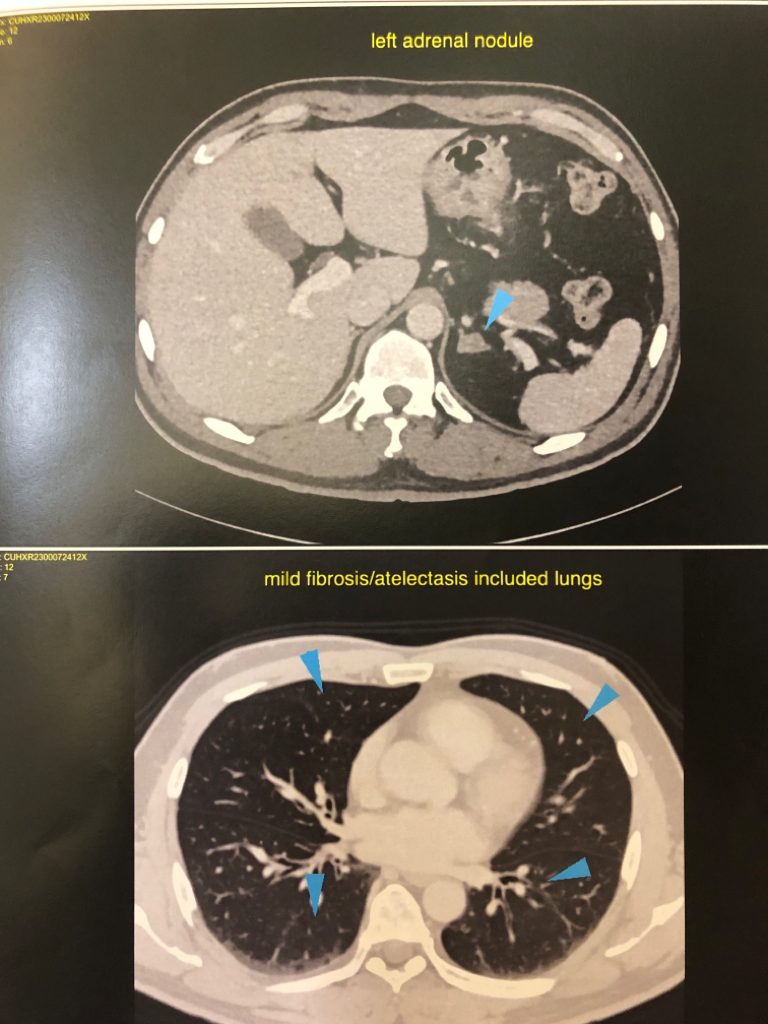

양쪽 부신에 낭종이 있고, 신장에 결석인지 물혹인지가 있고 폐 석회화,경증의 전립선 비대 등등이 있다고 알고 있는데요

• 1번 째 사진

• 2번 째 사진

• 3번 째 사진

• 4번 째 사진

• 5번 째 사진

• 6번 째 사진

• 7번 째 사진

• 8번 째 사진

• 9번 째 사진

굉장히 자세히 꼼꼼히 보시고 결과를 주신 것으로 보입니다(우리나라에서도 이 정도로 판독하시는 분은 드뭅니다). 검사결과를 설명할 때 괜찮은 결과는 언급을 잘 안 해드리는 경우가 많습니다.

췌장도 정상이라고 판독지에 언급이 되어 있습니다. 설명이나 판독이 불안하시다고 생각이 되면 CT 파일 전체를 가지고 다른 영상의학과 선생님께 재판독을 의뢰하는 방법이 있습니다만(사진이 굉장히 여러장이고 올리신 사진이 일부이기 때문에) 해외시면 쉽지 않은 방법으로 생각됩니다.